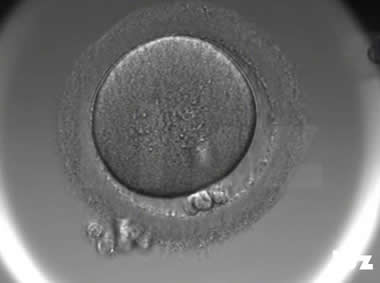

3. 成熟卵母细胞(MII)及其COCs(正常COCs)

卵细胞呈现规则的圆形且颜色较浅,放射冠完全分散,颗粒细胞团较大,排列稀疏。成熟卵母细胞一般在取卵后体外培养2-6小时再行授精。

|  |

| 0小时COCs的MII卵(4x) | 0小时COCs的MII卵(10x) |

|  |

| 2小时COCs的MII卵(10x) | 4小时去颗粒细胞后的MII卵(10x) |